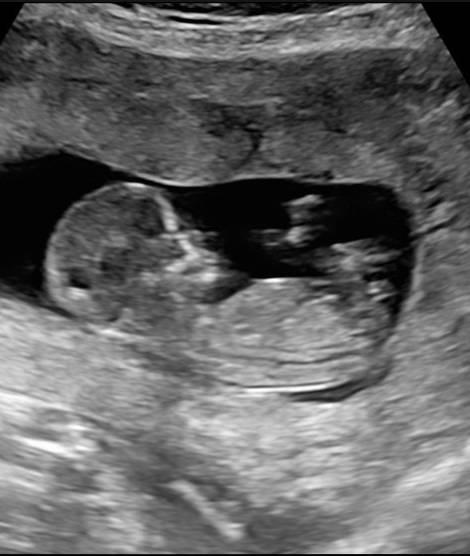

Die Ärztin meinte sie tippt auf ein Mädchen. Ich hab mich rießig gefreut. Ich spreche die kleine Maus schon weiblich an. Dann erinnerte mich mein Mann dass sie sagte sie täusche sich selten was meint ihr sieht es nach einem Mädchen aus ? Das Geschlecht laut praena Test dürfen sie mir noch nicht sagen.

Also, ich tippe auch auf ein Mädchen. Der Winkel des Geschlechtsteils ist weniger als 30 Grad und verläuft mehr oder weniger waagerecht zur Wirbelsäule. Das spricht für ein Mädchen, ist aber keine Garantie. Bei meiner Tochter sah es vor 2 Jahren in der 13. SSW gebauso aus und es hat gestimmt. Zudem sagt man auch, dass ein eher runder Kopf/Stirn eher für ein Mädchen spricht. Inwiefern das aber stimmt weiß ich nicht... Wann bekommt ihr denn das Ergebnis vom Praena-Test?

Hi, Danke das beruhigt mich . Das wäre ja die Nub Theorie. Bei meiner verstorbenen Tochter sah es auch so aus. In 10 Tagen soll ich nochmal anrufen LG